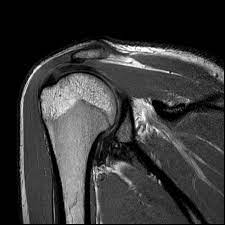

After months of suffering, Raj decided to consult a specialist. His doctor recommended a Musculoskeletal MRI, a cutting-edge diagnostic tool designed to provide detailed images of bones, muscles, joints, and soft tissues. Unlike traditional X-rays or CT scans, Musculoskeletal MRI offers a more comprehensive view, allowing doctors to pinpoint the exact issue with precision.

The results were enlightening. The MRI revealed a herniated disc pressing against a nerve, the root cause of Raj’s chronic pain. With this new information, his doctor was able to devise a targeted treatment plan, including physical therapy and medication, to address the specific issue.

For individuals like Raj, the Musculoskeletal MRI is more than just a diagnostic tool; it’s a beacon of hope. It provides clarity and a path forward, transforming lives by addressing the core of the problem. Whether it’s a persistent backache, unexplained joint pain, or muscle discomfort, this advanced imaging technique holds the key to unlocking a pain-free life.